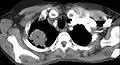

Diagnosis of Pancoast tumor is usually made after evaluating clinical symptoms and imaging. Chest X-ray is a good screening test even though a CT scan of the chest can provide a better resolution and extent to which internal organs are being compressed.